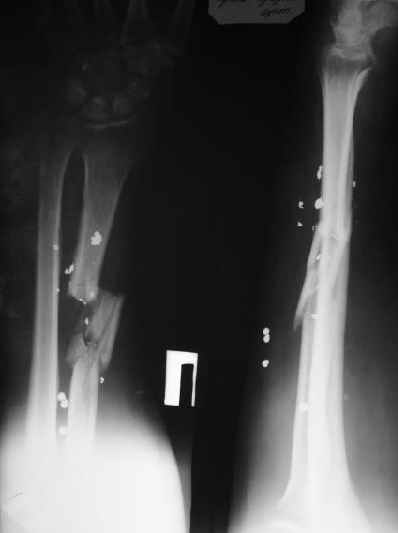

Мужчина 36 лет 5 мес. назад получил дробовое ранение правого предплечья с переломом лучевой кости, повреждением лучевой артерии и срединного нерва.

В больнице по месту жительства обрабатывали рану,сделали несвободную кожную пластику, синтезировали спицей интрамедуллярно, потом убрали. Свищей нет. Линейный рубец по лучевой стороне, приживший лоскут по ладонной (см. картинку).Cращение не произошло (см. снимок).Нейрохирурги что-то надеются сделать, но условием ставят стабилизацию лучевой кости.Какой вариант тут предпочесть? Представляется оптимальным аппаратом дозированно подправить длину и ось, и закрыто ввести интрамедуллярный стержень. Не особо даже рассчитывая на сращение, а только восстановить форму и длину кости, и создать "эндопротез диафиза". Или подумать про какие-то другие варианты?A male 36 years old 5 month ago sustained a gun-shot wound with the radial fracture and lesion of a.radialis and n.medianus. Debridement was performed at the initial hospital, full-thickness skin grafting and intramedullary fixation of the radius by a small wire, which later was removed. No sinuses and signs of infection to date. A linear scar on the radial side and the healed flap (see image). Healing was not reached (see x-rays).Neurosurgeons hope to do something with the peripheral nerves but only in case of stabilization of the radius.Which treatment modality should be preferred? I would perform gradual alignment with the Ilizarov, and perform secondary closed nailing. Even not to expect to reach union, just to restore length andalignment with the "shaft endoprosthesis". Or it is worth to think about other options?

Судя по фотографии, у пациента были повреждены не только срединный нерв и лучевая артерия, но и сгибатели -- на уровне перехода мышц в сухожилия.

Насколько клинически выражена нестабильность в зоне перелома? Такое впечатление, что сращение все-таки идет, пусть и медленно, и со смещением отломков. Нельзя ли посмотреть рентгенограммы в динамике?